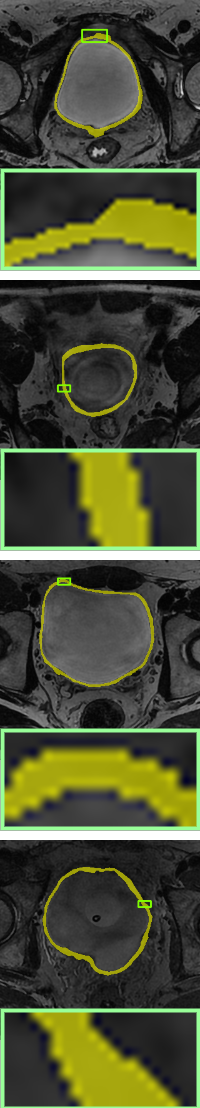

In this section, we will add two different topological energies to Topo-NLSTD model Eq. 13. For convenience, when adding energy without width information Eq. 11, it is denoted as PH; when adding width-aware topological energy Eq. 12, it is denoted as WT. Fig. 7, Fig. 8 and Fig. 9 show the results on synthetic images, the International Symposium on Image Computing and Digital Medicine (ISICDM) 2019 dataset [isicdm] and the Massachusetts Roads dataset [mass], respectively. From the results, we can see that NLSTD retains more image information compared to STD rather than performing a simple smoothing. Then, the results of PH are usually connected to a single-pixel width line or a single-pixel genus to satisfy a given topological constraint. In contrast, our proposed energy not only maintains the topological consistency well, but also fuses the width information.

Image

UNet[unet]

STD[std]

NLSTD[densecrf]

PH[ph]

Proposed WT

Magnetic resonance imaging-based segmentation of the inner and outer bladder wall dataset [isicdm] is from the Third International Symposium on Image Computing and Digital Medicine, which is called the ISICDM dataset. We select images from the dataset that are single-connected and contain one genus and divide them subsequently into training (480), validation (80) and test (120) sets. The size of each image in the dataset is 512 × 512, and the goal is to achieve accurate segmentation of the inner and outer boundaries of the bladder.

We compare the results of no topological constraints (without-topo), topological constraints without width (PH), and width-aware topological constraints (WT) applied to a number of data-driven models for relevant applications. As can be seen in Table 3, our proposed method (rows with gray background) shows superior performance. Specifically, the improvements in volumetric demonstrate that our method has more accurate result in a pixel-level sense, while the improvements on topology-based metrics demonstrate that WT energy has an overall more precise prediction and topological similarity. For boundary-based indicators, WT performs better compared to PH in most cases due to the width information. The corresponding visualization is given in Fig. 10 and Fig. 11. From the visualization results, it can be seen that in data-driven image segmentation models, no topological constraints will produce obvious topological errors, even if its segmentation results have high accuracy. When constraining topological consistency using persistent homology methods, it may be possible to connect very thin lines to ensure connectivity or a consistent number of holes. We improve the PH method by smoothing the critical points in there structuring elements neighborhood, which can preserve the width information while constraining the topological properties to be consistent.